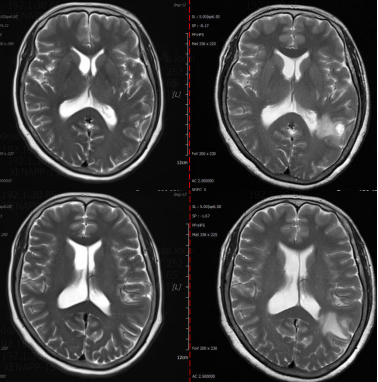

头颅MRI(2023年11月17日):左侧额顶叶皮层下结节伴周围脑水肿,考虑脑转移瘤可能。

图片3.png

头颅MRI基线(2023年11月17日)

• 2024年5月24日:影像学评估为完全缓解(CR),原发灶及转移灶均明显消退。

图片4.png

胸部CT(左:2023年11月12日;右:2024年5月24日)

图片5.png

头颅MRI(左:2024年5月24日;右:2023年11月17日)